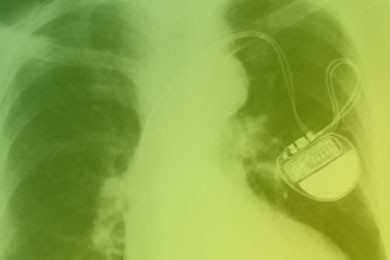

Le premier pacemaker